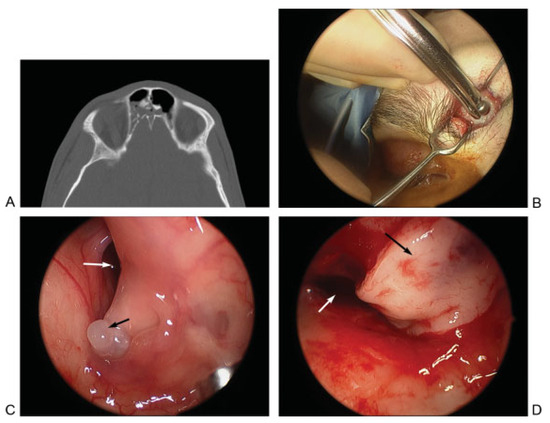

Figure 6.

(A, B) Axial and coronal computed tomographic (CT) images demonstrating a fracture involving the posterior table of the left frontal sinus. Fluid is also seen in the sinus. (C, D) Postoperative axial and coronal CT images demonstrating a well aerated and healed frontal sinus after use of a trephination for repair of the cerebrospinal fluid leak resulting from the defect. The axial image shows the titanium mesh used for reconstruction of the defect resulting from the entry into the frontal sinus.